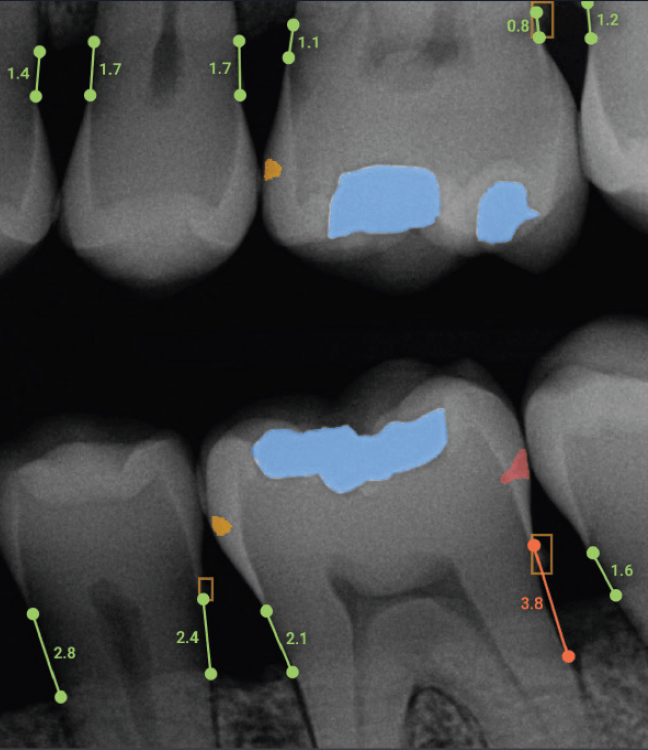

Overjet X-Ray

Overjet is an artificial intelligence (AI) dental software platform that analyzes dental X-rays (radiographs) to automatically detect, outline, and quantify dental conditions such as decay, bone loss, and tartar (calculus) in real time. It creates a color-coded, annotated overlay on top of traditional, black-and-white dental X-rays to help patients and dentists visualize the findings.